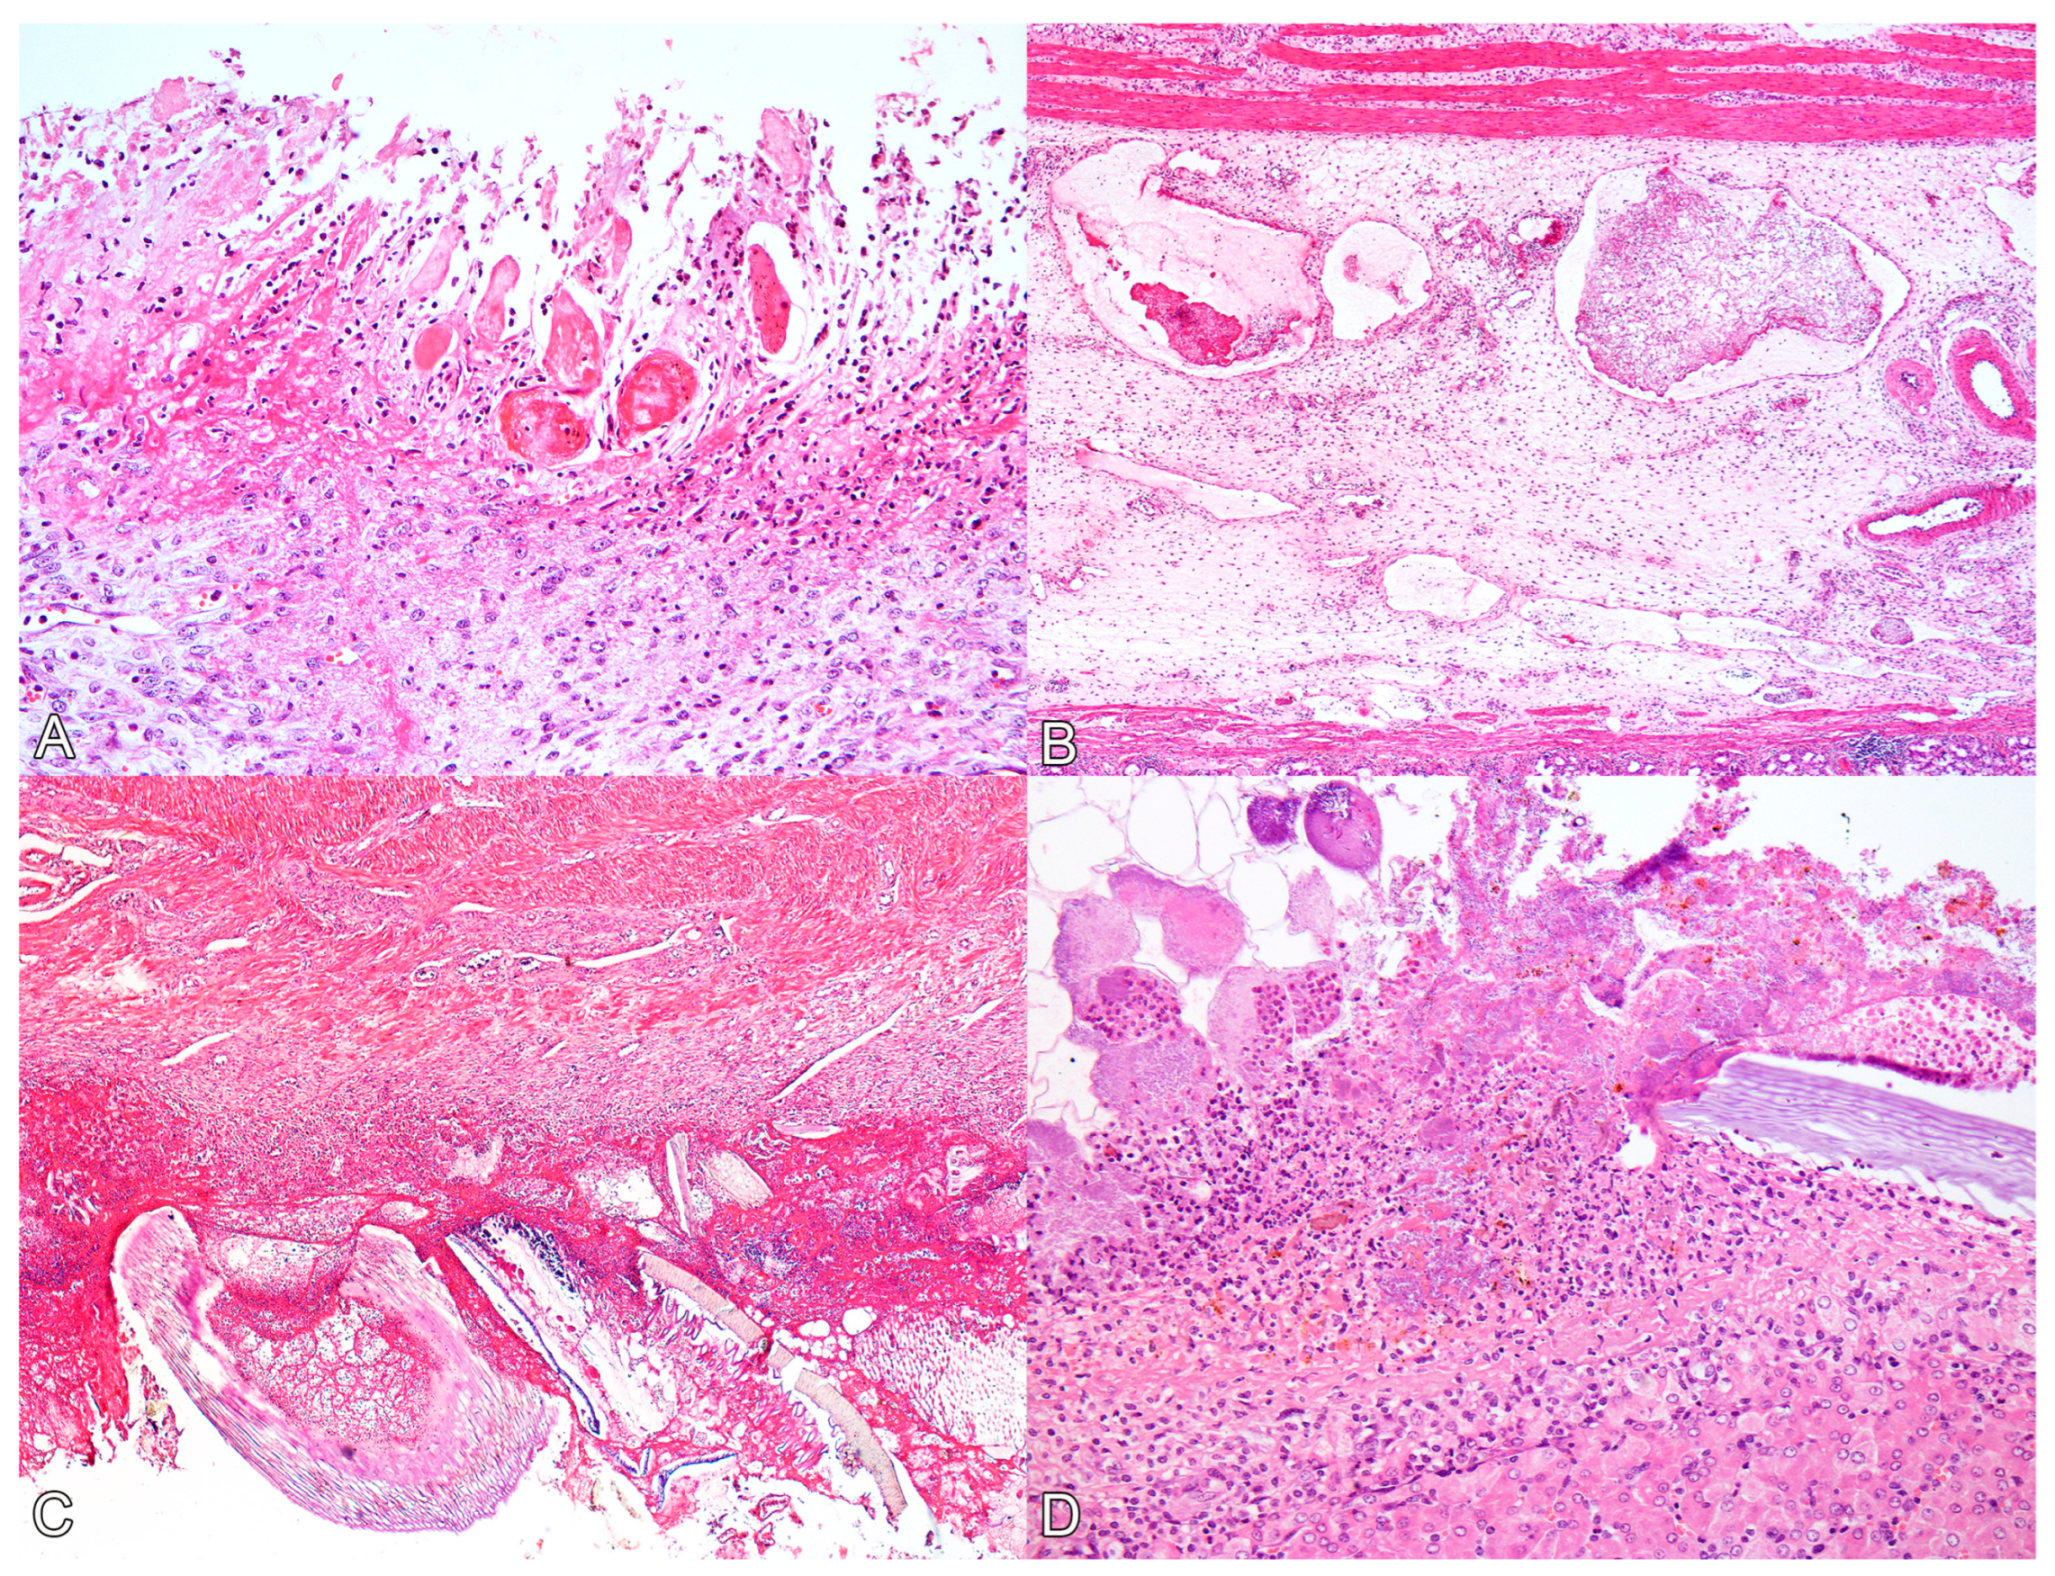

Histologically, the main lesions were observed in the glandular stomach. In the mucosa of the glandular stomach of all pigs, there was marked ulceration (Figure 2A), characterized by necrosis of the epithelium and tissue discontinuity, along with pronounced inflammatory infiltrate of neutrophils, deposition of fibrin, and coccobacillary bacterial myriad. The inflammatory infiltrate extended into the submucosa and muscular layers, where it was associated with severe edema and vascular thrombosis (Figure 2B). Additionally, multiple fibrin thrombi were observed within lymphatic vessels in the submucosa. The mucosa adjacent to the ulcerations exhibited marked congestion. In the mucosa of the pars esophagea (aglandular stomach) and esophagus, all animals displayed moderate and diffuse parakeratotic hyperkeratosis, accompanied by multifocal areas of erosion in the cardia (swine 1 and 4) and esophagus (swine 2 and 3).

Figure 2. Histological lesions of perforated ulcerative gastritis in swine associated with acute oral chromium exposure. (A) Stomach. There is diffuse necrosis of the glandular mucosa, characterized by loss of tissue and cellular architecture and associated with hyperemia, neutrophil infiltration, and fibrin deposition. Swine 3. HE, 200×. (B) Stomach. The submucosa exhibits marked edema, and lymphatic vessels appear ectasic and filled with fibrin thrombi. Swine 3. HE, 100×. (C) Stomach. On the serosal surface, there is marked fibrin deposition, infiltration of neutrophils, bacterial myriad, and fragments of plant fibers from the gastric content. Swine 4. HE, 100×. (D) Liver. The Glisson’s capsule shows marked fibrin deposition, neutrophil infiltration, and bacterial myriad. A plant fiber is also noted amidst the lesion. Swine 4. HE, 200×.

On the serosal surfaces of the stomach (Figure 2C), small and large intestines, and urinary bladder (as well as in the hepatic (Figure 2D) and splenic capsules), there was marked fibrin deposition, along with abundant plant fibers. Additionally, inflammatory infiltration of neutrophils and coccobacillary bacterial myriad were noted.